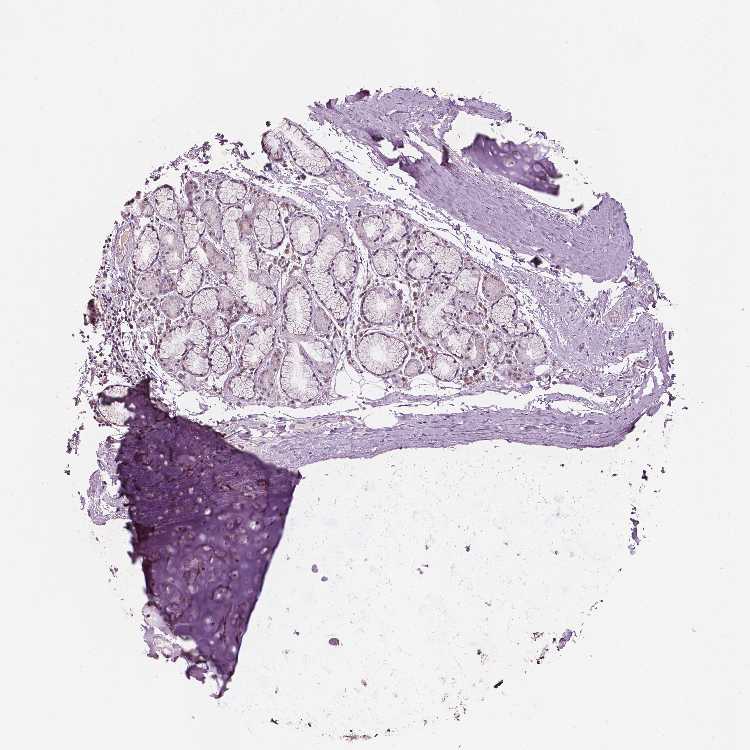

SOFT TISSUE 2 - Antibody stainingi

Antibody staining in the annotated cell types in the current human tissue is reported as not detected, low, medium, or high, based on conventional immunohistochemistry profiling in selected tissues. This score is based on the combination of the staining intensity and fraction of stained cells.

Each image is clickable and will lead to virtual microscopy that enables deeper exploration of all samples and also displays staining intensity scores, fraction scores and subcellular localization as well as patient and tissue information for each sample.

Antibody HPA067973

Fibroblasts Not detected

Peripheral nerve Not detected